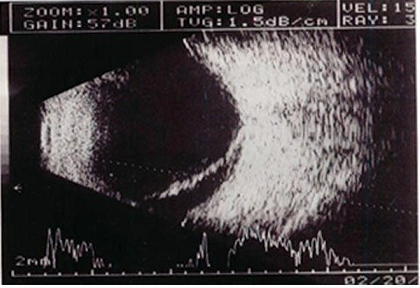

患者,女,14岁,眼部外伤两小时。超声检查如图,最可能的诊断为()。

A.玻璃体积血

B.玻璃体混淆

C.脉络膜脱离

D.视网膜脱离

E.以上均不是